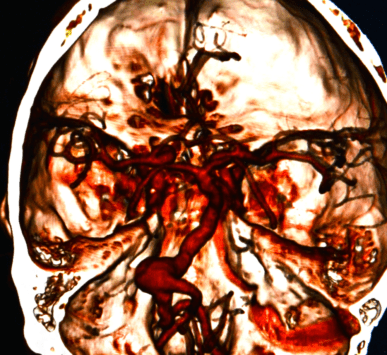

An aneurysm is a bulging of a blood vessel wall caused by a weak point and can be located in the aorta or brain, it may burst and thereby lead to potentially fatal bleeding.

There is one type of stroke that results from internal bleeding in the brain, and it is referred to as a brain hemorrhage. t is usually caused by the bursting of a blood vessel

Stroke occurs when part of the blood supply to the brain is cut off, resulting in cell damage. It may be hemorrhagic (bleeding) or ischemic (clot).